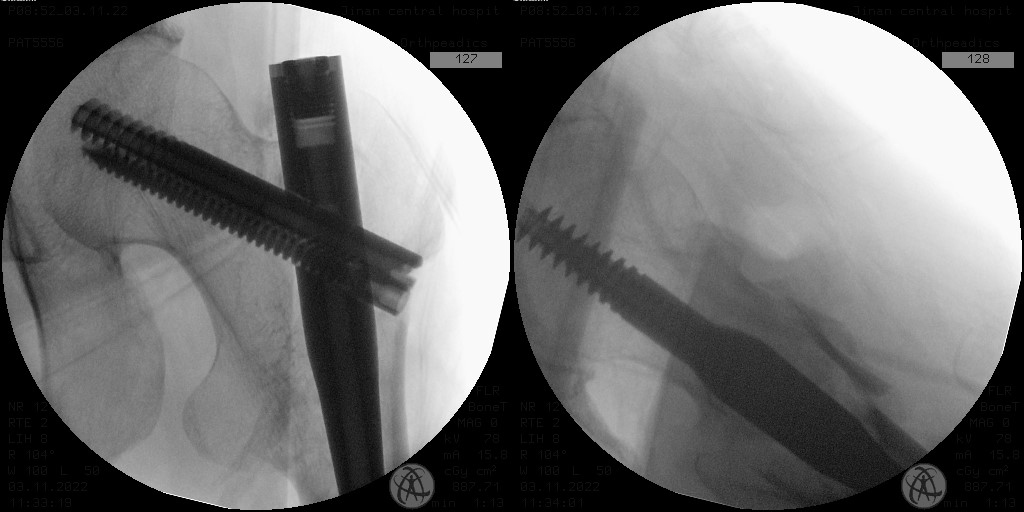

难复性股骨转子间骨折真实面目是X线片正位骨折对位可以接受,侧位骨折矢状位不稳,骨折近端向前方、骨折远端向后方成角移位,该患者更为复杂的是骨折断端前方有游离骨折片,常规钳夹复位方式可能会导致骨折片异常嵌插或再骨折。高长虹主任医师、林涛副主任医师团队经过周密仔细的术前讨论和准备,如期为患者行手术治疗,术中采取骨折近、远端分别予以微创复位方式,完成髓内钉内固定手术,X线正、侧位骨折对位对线良好,骨折断端前方骨折片位置良好,术中及术后后透视图像如下:

*术后